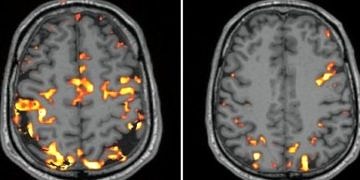

İnsan beyni doğanın en karmaşık sistemlerinden birisi ve bu nedenle üzerine en çok çalışma yapılan organlarımızdan bir tanesi. Bu nedenle...